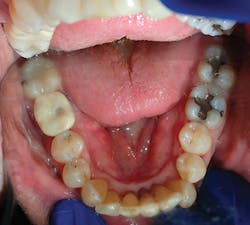

Being a network of small- to medium-sized private practice groups, we negotiated volume pricing on our favorite suite of manufacturer-direct systems. It is these systems that were uncovered during this process that we will highlight in the clinical portions of this series. We secured high-volume, manufacturer-direct, DSO-like pricing, and we call ourselves the Implant Alliance.In our practice of four dentists in Allen, Texas, we have been very intentional about making sure we can deliver incredibly high-quality dentistry at affordable rates for our patients. The case shown this month (figures 7–12; courtesy of Mike Dostal, DDS, FICOI) represents a very typical “I just need my tooth replaced” kind of day in our office. You see a patient in hygiene who has been missing a tooth for years and just didn’t want a bridge. Now, we can offer a simple appointment to place a flapless, sutureless implant, and the patient probably can go right back to work the same day.

The implant systems that satisfy this challenge the best for us are the iHex 1, 2, and 3 and MorsTorq systems by iH Biomedical. The iHex series is an internal hex that is compatible with most of the major internal hex systems. It incorporates platform switching, which allows for crestal or subcrestal placement. The designers created a multicompatibility surgical kit that minimizes the number of drills (often just one needed) used to place and restore the implants. The platforms are the same across most sizes, which reduces the number of abutments that must be stocked. Also, the implant, abutment, and cover screw are all included. These design features place this system at the top of the list when it comes to economics and excellence rolled into one package.